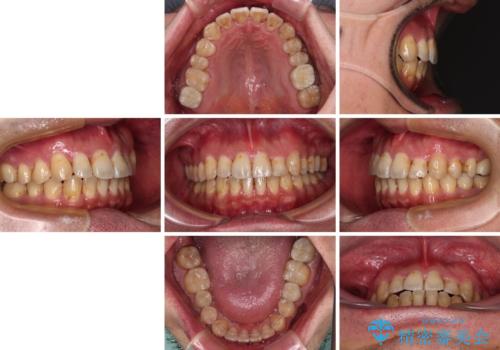

インビザライン矯正では苦手とする舌側転位した前歯をスムーズに改善することができました。

矯正治療により歯磨きがしやすくなったので、虫歯予防のセルフケアが行いやすい環境となりました。